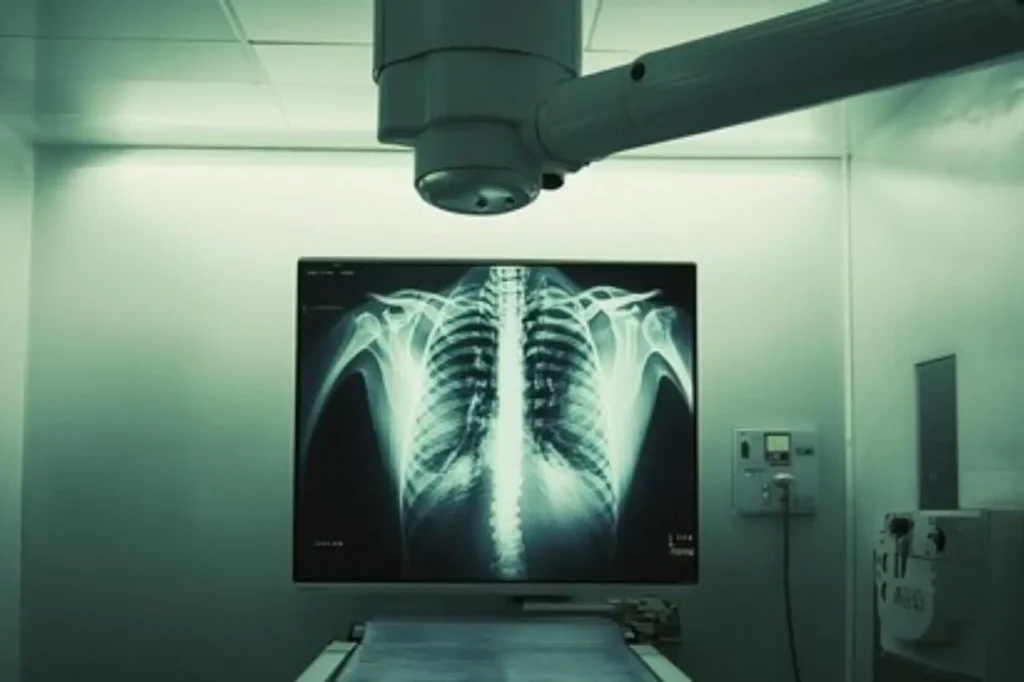

Radiology Services at Quironsalud Hospital Dubai: Cutting-Edge Diagnostic Imaging

Radiology is the cornerstone of modern diagnostics, enabling accurate and early detection of various health conditions. At Quironsalud Hospital Dubai, our radiology department leverages advanced imaging technologies to provide patients with precise results and tailored care. From routine screenings to specialized diagnostics, we ensure a seamless experience.

- Digital X-Rays: Quick and effective imaging to assess bone fractures, lung conditions, and more.

The Role of Radiology in Healthcare

Radiology plays a vital role in identifying diseases at their earliest stages. Whether it’s detecting cancer, monitoring chronic conditions, or guiding minimally invasive procedures, imaging technologies are essential for accurate treatment planning and better patient outcomes. At Quironsalud Hospital Dubai, our radiology department is committed to enhancing diagnostic precision for all our patients.